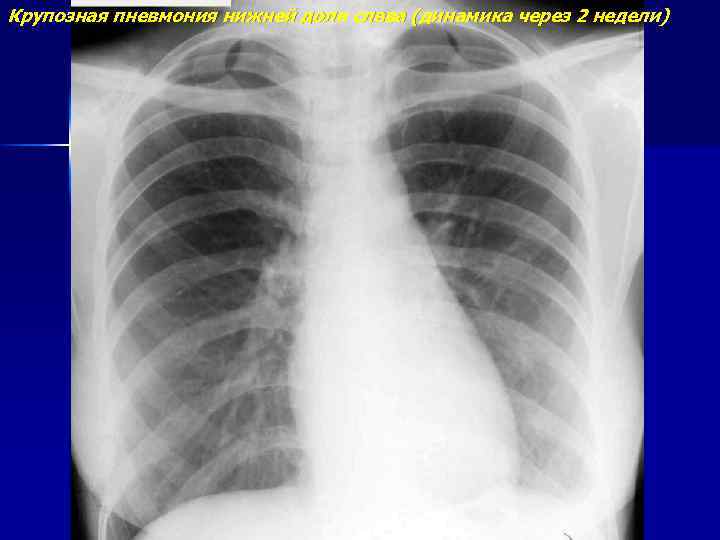

Крупозная пневмония нижней доли слева (динамика через 2 недели)